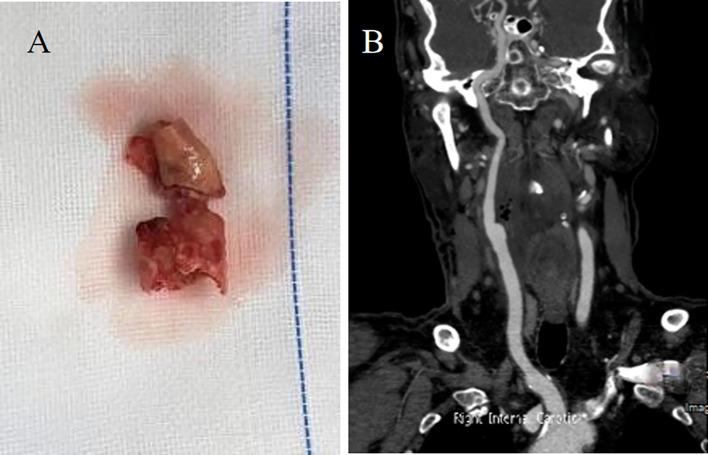

Severe headache as the initial clinical manifestation of early neurological deterioration (END) is uncommon. The emergence of severe headache should be promptly recognized as a potential indicator of large vessel stenosis. Here, we describe a male patient who initially presented with severe headache accompanied by transient left limb weakness, which subsequently progressed to persistent weakness. Imaging studies revealed severe stenosis at the origin of the right internal carotid artery, along with the presence of asymmetrically prominent cortical veins (APCV). Despite the administration of pregabalin orally and tramadol intramuscularly, his headache persisted. However, significant alleviation of his headache symptoms was observed following the improvement of cerebral perfusion. Re-examination revealed the resolution of cortical vein dilation. This case underscores the importance of recognizing severe headache and APCV as potential indicators of large vessel stenosis and early neurological deterioration (END). Improving cerebral perfusion may serve as an effective means of alleviating headache symptoms in such cases.

严重头痛作为早期神经功能恶化(END)的初始临床表现并不常见。严重头痛的出现应迅速被识别为大血管狭窄的潜在指标。在此,我们描述一名男性患者,其最初表现为严重头痛并伴有短暂性左下肢无力,随后进展为持续性无力。影像学研究显示右颈内动脉起始处严重狭窄,同时存在不对称突出的皮质静脉(APCV)。尽管口服了普瑞巴林并肌肉注射了曲马多,他的头痛仍持续存在。然而,随着脑灌注的改善,观察到他的头痛症状明显缓解。复查显示皮质静脉扩张消失。该病例强调了将严重头痛和APCV识别为大血管狭窄和早期神经功能恶化(END)潜在指标的重要性。改善脑灌注可能是缓解此类病例头痛症状的有效手段。